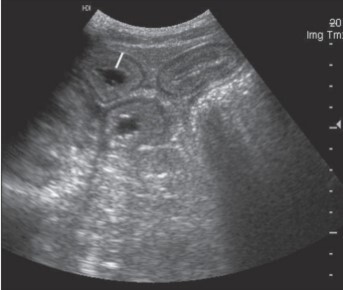

What pathogen causes equine proliferative enteropathy (thickened small intestine on ultrasound scan)?

A

Lawsonia intracellularis bacteria